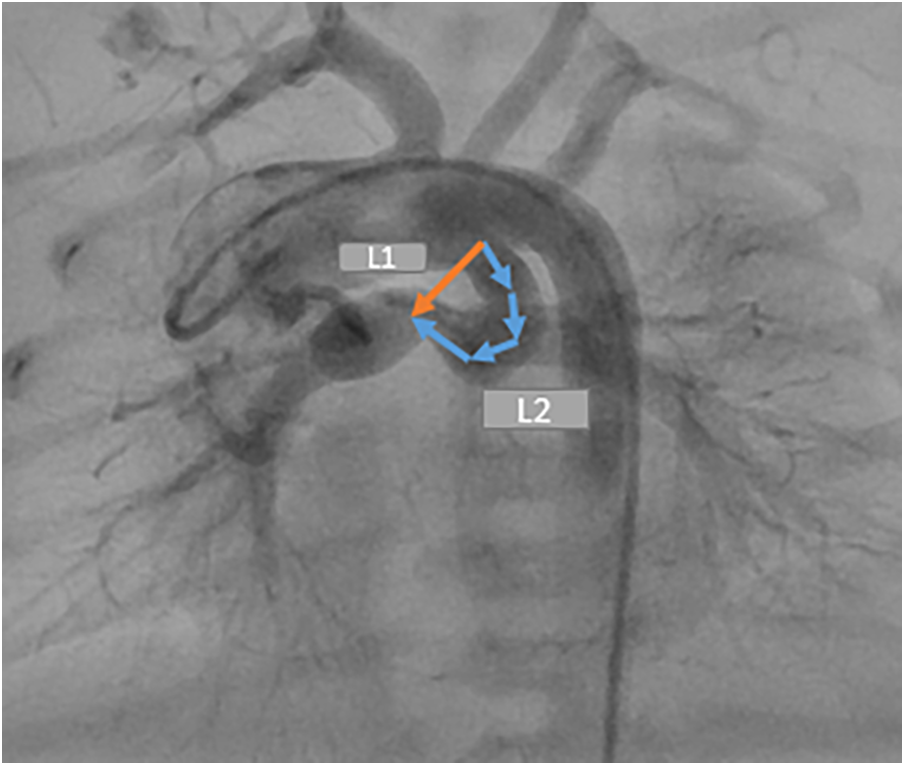

The DCI is a quantitative measurement of ductal tortuosity first reported by Qureshi et al. in 2019. It determines the severity of the ductal tortuosity. Two distances are required to measure DCI (L2 and L1). L2 is the entire length between the ductal origin and the ductal insertion onto the pulmonary arteriy. L1 is the straight, short distance between the two points (Figure 2).

Figure 2

Demonstration of two distances required for measuring the ductal curvature index. DCI = L2–L1/L2.